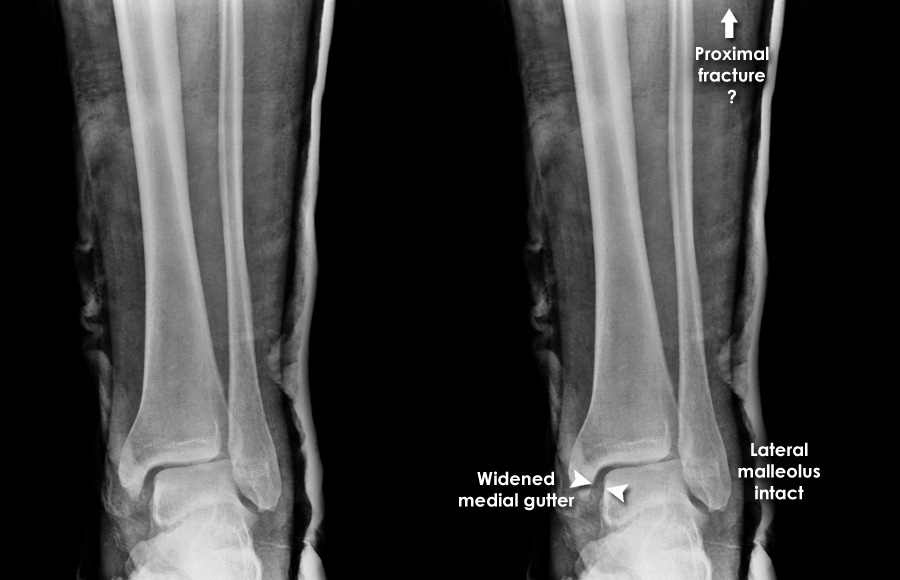

Ankle radiographs are used to detect widening of the tibiofibular syndesmosis or medial clear space. The medial clear space is the area between the talus of the ankle and the medial malleolus. Damage to the deltoid ligament and syndesmotic ligaments result in mortise instability, causing the talus to laterally shift and widen the medial clear space. A clinical study, conducted in 2006 and published in the Journal of Bone and Joint Surgery, found that the medial clear space size of a normal ankle and an injured ankle measured at 4 millimetres and 5.4 millimetres in length respectively. To confirm diagnosis, full-leg radiographs are used to inspect for fractures of the proximal fibula and widening of the interosseous clear space (or tibiofibular clear space). The interosseous clear space is the area between the medial side of the fibula and lateral side of the tibia. A peer-reviewed study, published in Injury in 2004, found that an interosseous clear space greater than 10 millimetres indicates diastasis of the syndesmotic ligaments.

If necessary, computed tomography (CT) or magnetic resonance imaging (MRI) may also be used to clarify diagnosis. MRI scans can check for interosseous membrane or tibial tubercle damage if high instability of the ankle is diagnosed. Arthroscopy may be used to diagnose a syndesmotic lesion but is often not recommended due to operative difficulty. Stress radiographs of the ankle are used to assess the integrity of the deltoid ligament and tibiofibular syndesmosis. The size of the medial clear space can also be measured using stress radiography.